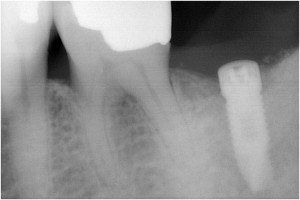

術前パノラマ写真